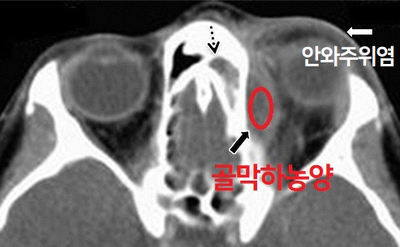

안와내 합병증 유형 합병증 진행 과정과 염증의 파급 정도에 따라 안와주위염, 안와봉와직염, 골막하농양, 악와농양, 해수면정맥동혈전, 안와첨증후군으로 구분합니다.

안와주위염 안와주위염은 염증이 안와격막 앞쪽에 한정되어 있어 전체 안와내 합병증의 80% 이상을 차지하고 있습니다.위의 사진과 같이 안검의 종창, 홍반이 나타납니다.

안와직염 안와봉와직염은 안와를 채우고 있는 연부조직까지 염증이 파급된 상태이며 결막부종, 안구돌출, 통증, 안근마비, 그리고 시력감퇴를 초래할 수 있습니다.

골막하농양의 CT영상골막하농양은 안와를 둘러싼 골막과 부비동골벽 사이의 농양으로 골막하농양이 안와 안쪽에 농양을 형성하면 안와농양이 됩니다.증상은 안와직염과 유사하며 안근, 시신경의 손상이 커서 시력소실을 유발할 수 있습니다.